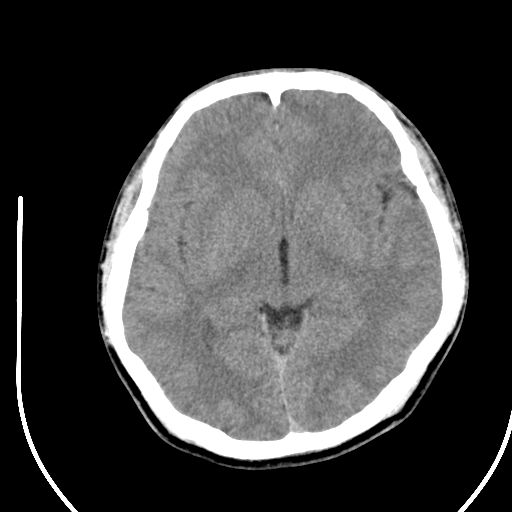

标题: CT28158:男,27Y。头痛数月,左顶叶血管瘤。 [打印本页]

标题: CT28158:男,27Y。头痛数月,左顶叶血管瘤。

考虑左顶叶海绵状血管瘤,建议mr检查。

左侧额叶海绵状血管瘤可能性大;建议行mri检查。

考虑血管畸形,因其周可见水肿,不除外感染性病灶。建议mri检查。